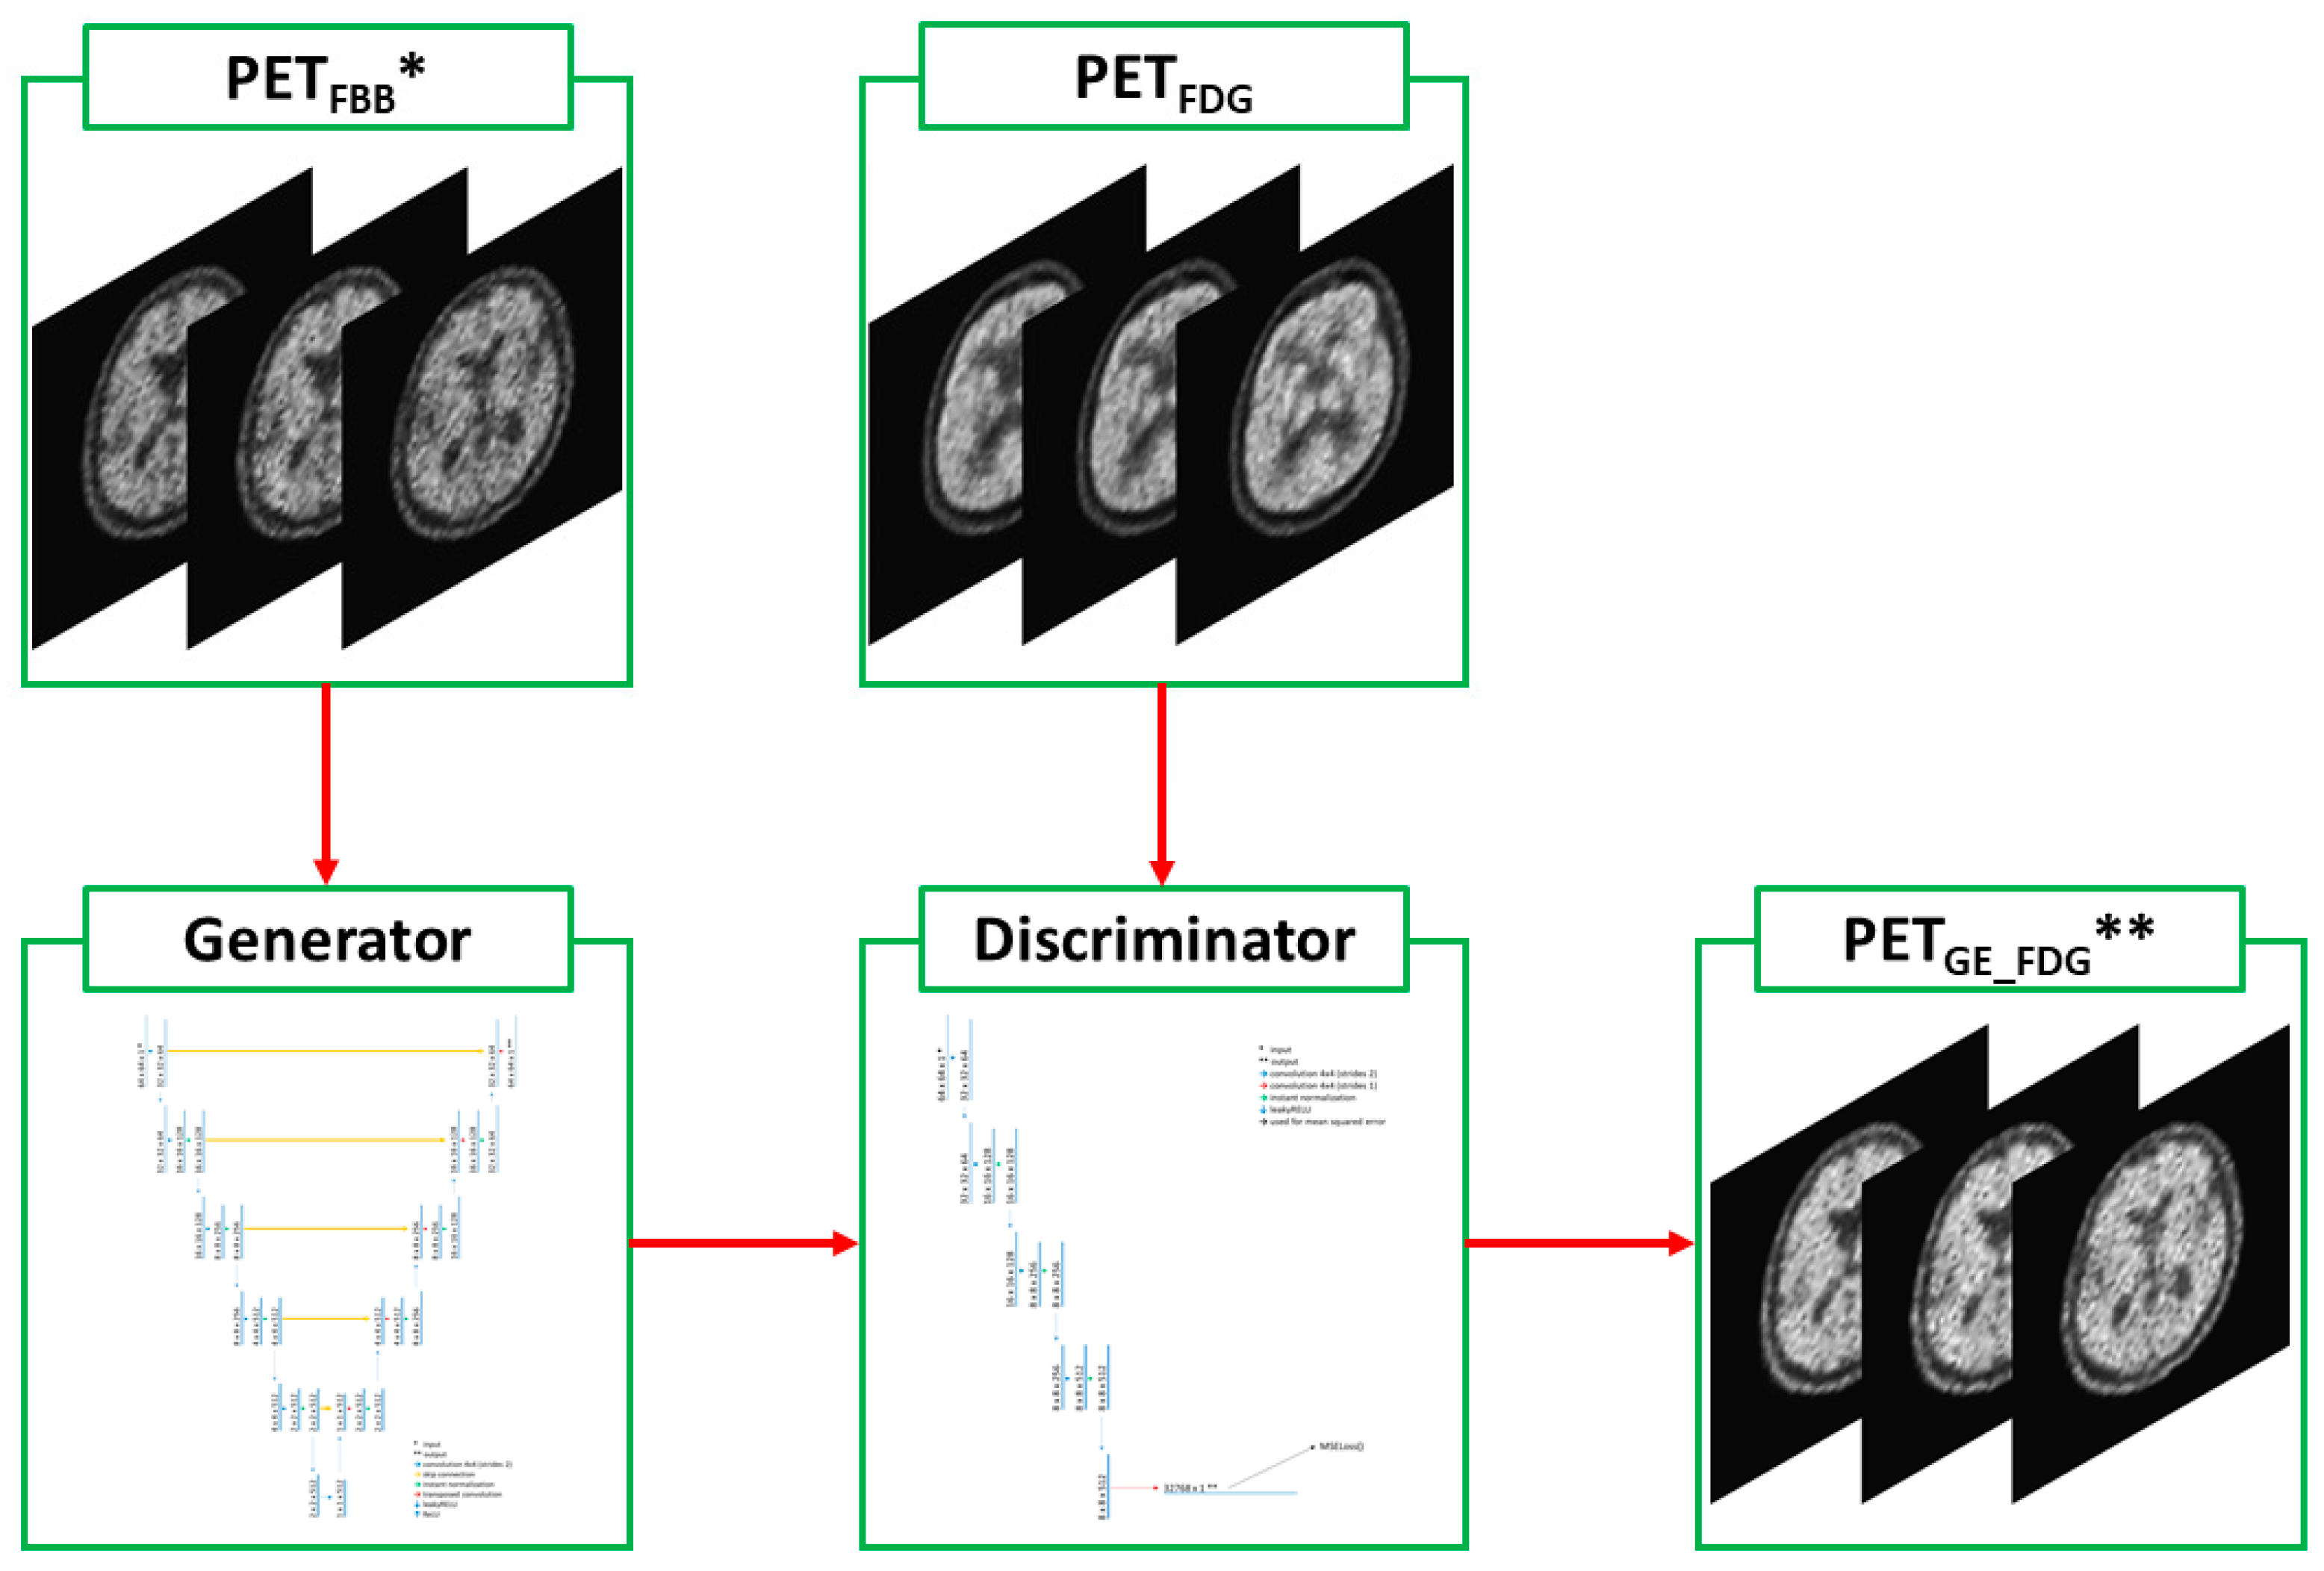

2.2. Deep-Learning Model with Image Preprocessing